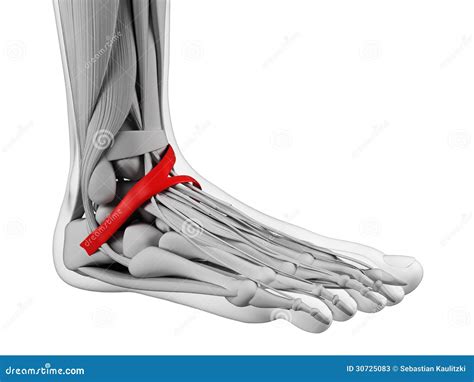

Structures Protected by the Flexor Retinaculum

Beneath the flexor retinaculum lies the tarsal tunnel, a narrow space through which several vital components pass. If the retinaculum becomes thickened or inflamed, it can compress these structures, leading to discomfort. The following structures pass through this passage, often remembered by medical professionals via specific mnemonics:

• Tibialis Posterior Tendon: Located most anteriorly, essential for supporting the arch of the foot.

• Flexor Digitorum Longus Tendon: Responsible for curling the toes.

• Posterior Tibial Artery and Veins: Provide essential blood supply to the foot.

• Tibial Nerve: The primary nerve providing sensation to the sole and motor function to foot muscles.

• Flexor Hallucis Longus Tendon: Positioned most posteriorly, responsible for flexing the big toe.